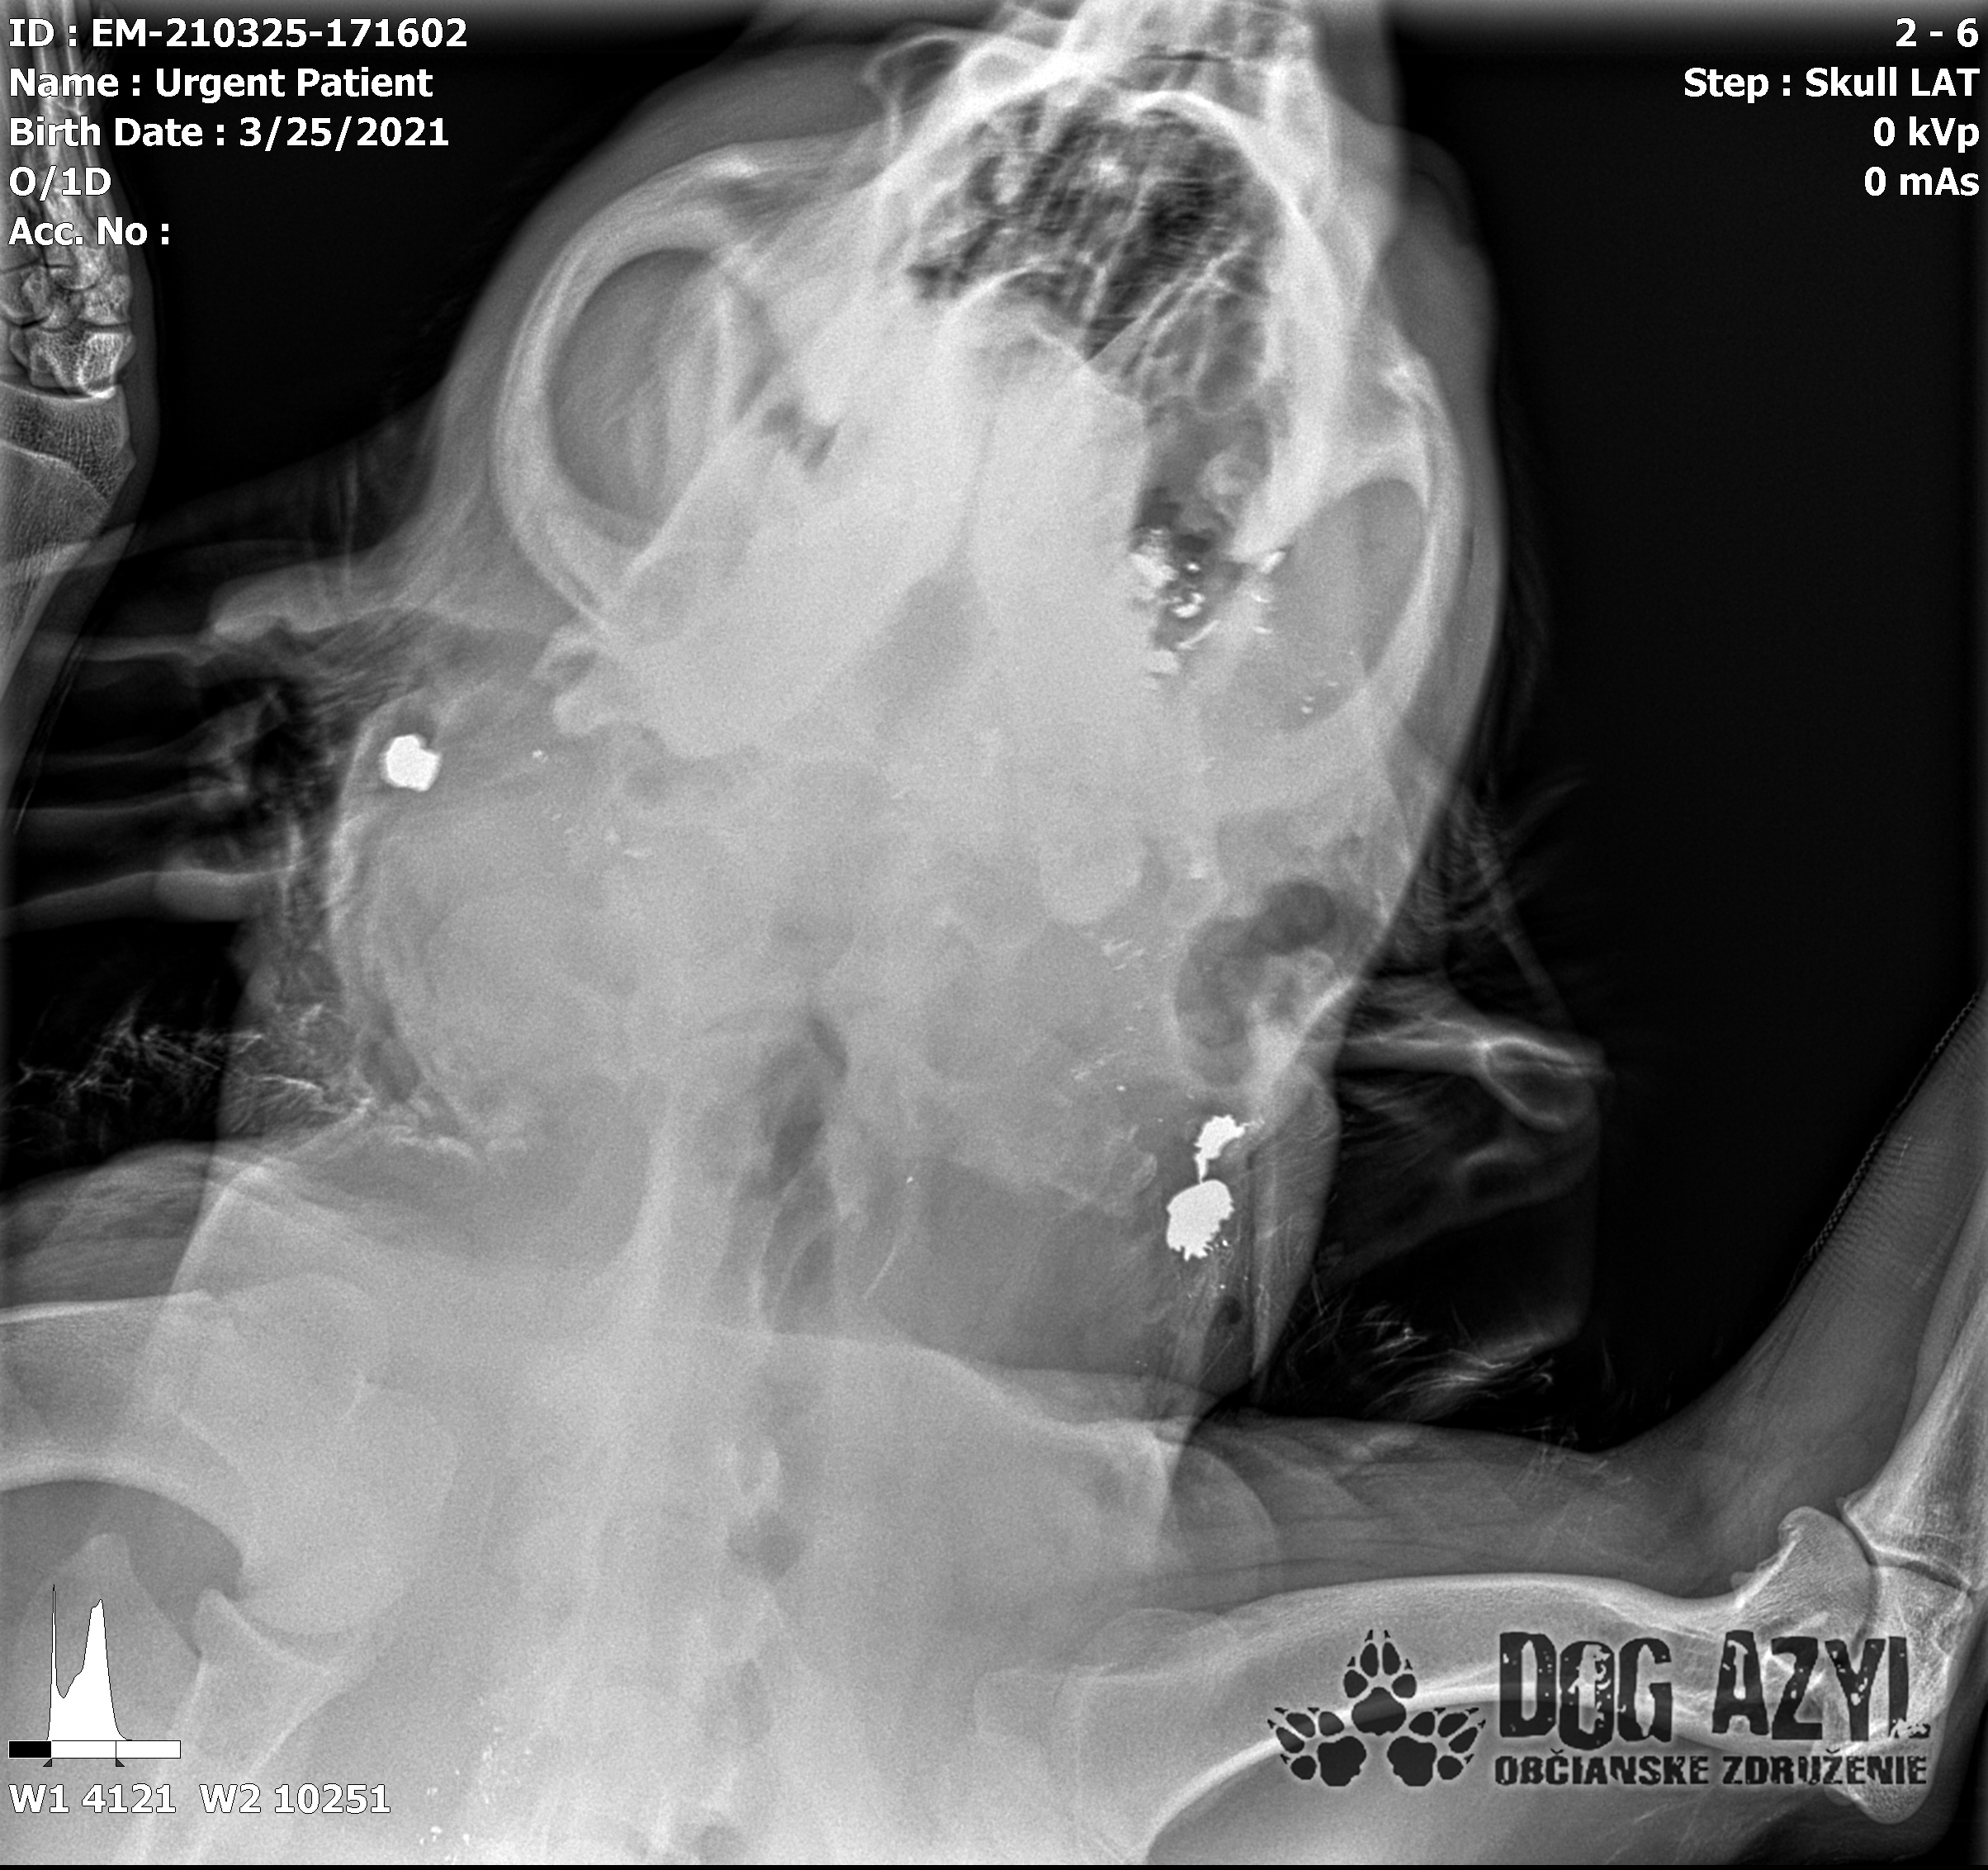

Strela zasiahla Barisa v oblasti lícnej kosti, ktorá mu rozdrvila sánku a následne putovala cez krk až po krčnú chrbticu. Úlomky z guľky (neviem ako sa to odborne volá) sa roztrieštili na "milión" kusov počas svojej cesty. Tieto úlomky sú všade (ako vidieť aj na RTG). Jeden (alebo niekoľko týchto úlomkov) sa dostali až po miechu, ale našťastie ju neprerazili. Toto spôsobilo, že Baris citlivosť v nohách na ľavej strane sice má, ale má poškodenú motoriku. Tieto úlomky sa z oblasti stavcov, miechy aj krku dnes odstránili, ale Barisko z ďaleka nemá vyhraté. Miecha je totiž zakrvácaná (opäť sa ospravedlňujem za nepresnosť a laickosť) a to, že ako veľmi je poškodená, alebo či jeho slabosť bola spôsobená "iba opuchom" sa ukáže cca do 24 hodín. Ak Baris nedajbože do zajtra stratí citlivosť v nohách, tak.. žiaľ... Ale! ak citlivosť zostane, prípadne nastane aj zlepšenie, tak vzplanie plamienok ďalšej nádeje a bojujeme ďalej!